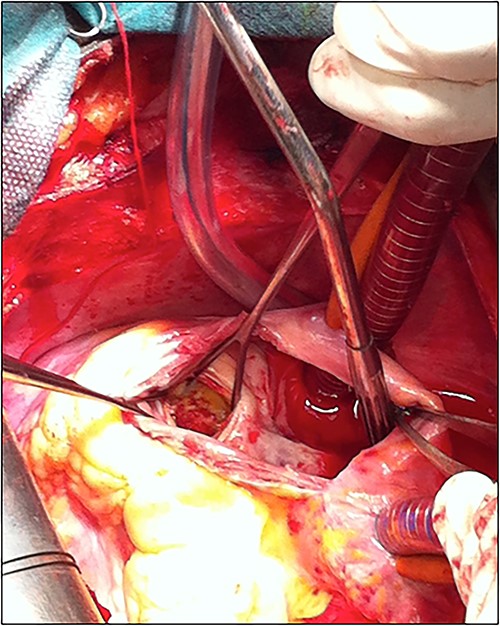

The patient underwent cardiac surgery with a median sternotomy approach and cardiopulmonary bypass. Exploration confirmed the presence of a giant aneurysmal formation originating from the LCX and communicating with the RA. After aortic clamping, a right atriotomy was performed. The aneurysm was opened, then both communications (to the LCX and the RA) were closed using two autologous pericardial patches. A third patch was used to close the aneurysm after partial resection (Fig. 5).